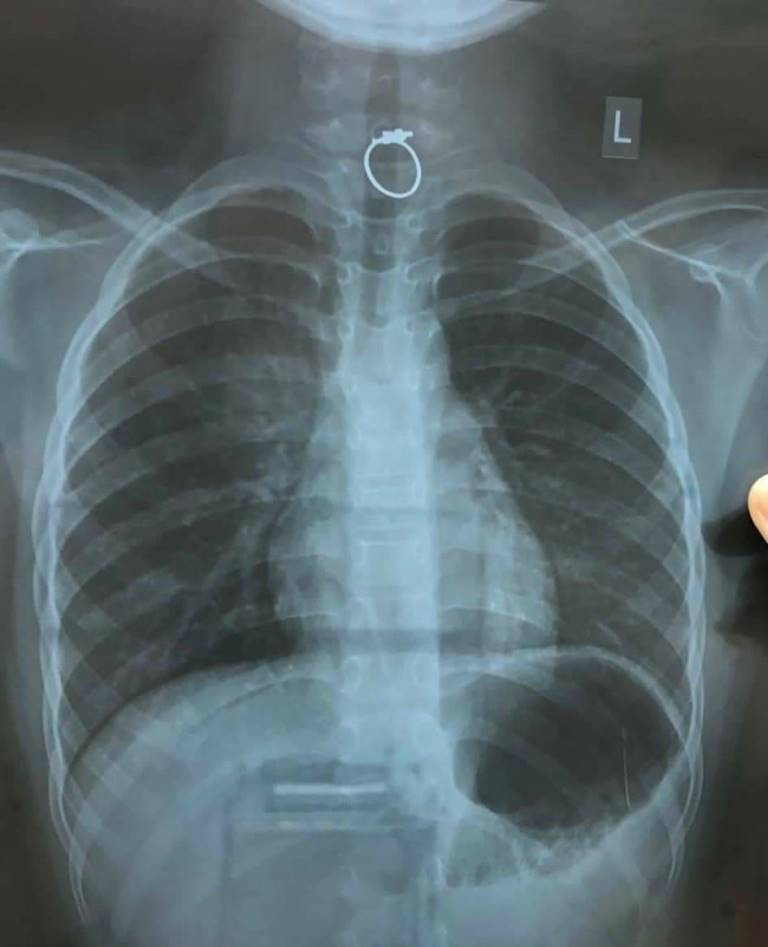

Được tặng nhẫn, bé gái nuốt trôi xuống họng ảnh 1Hình chụp cho thấy chiếc nhẫn còn vướng trên thực quản của trẻ (ảnh:BVCC)

BS Lê Đức Lộc, khoa Tiêu Hoá được điều động vào Bệnh viện cùng ekip gây mê trực Tết, nội soi gắp kịp thời khi chiếc nhẫn chắn ngay 1/3 trên thực quản.